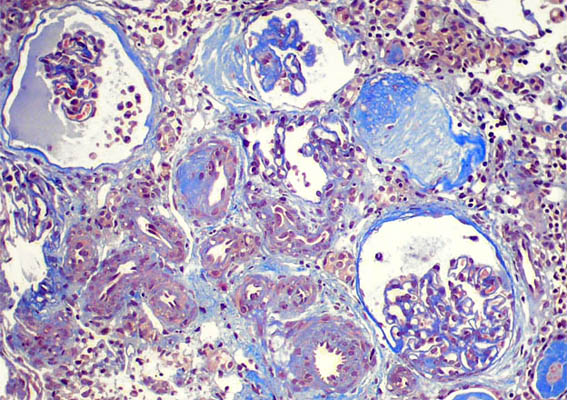

Figura 2.

Plata-metenamina, X200.